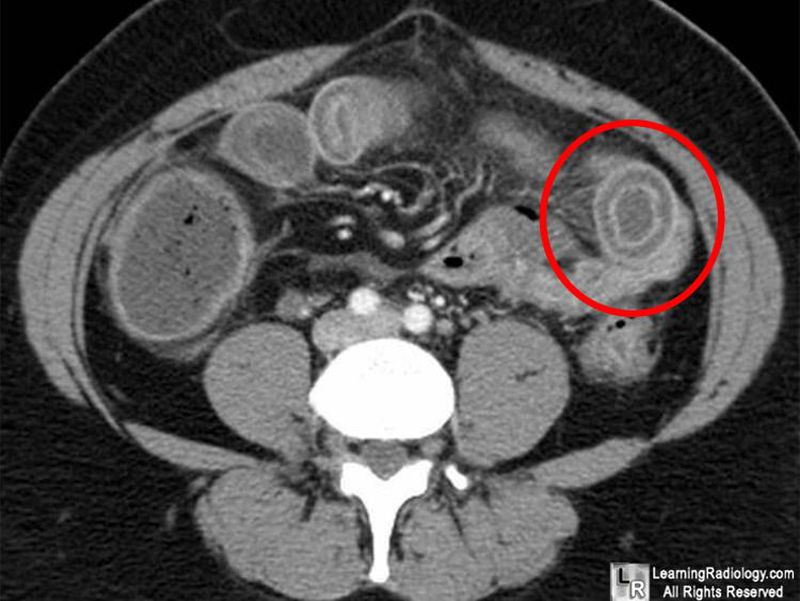

In which disease we see that? 1.appendicitis 2.diverticulitis 3. intussusception 4.colon obstruction

Any inflammatory pathology of bowel wall such as Crohn’s disease, ischemic colitis, radiation induced colitis, ulcerative colitis or C. difficile colitis.